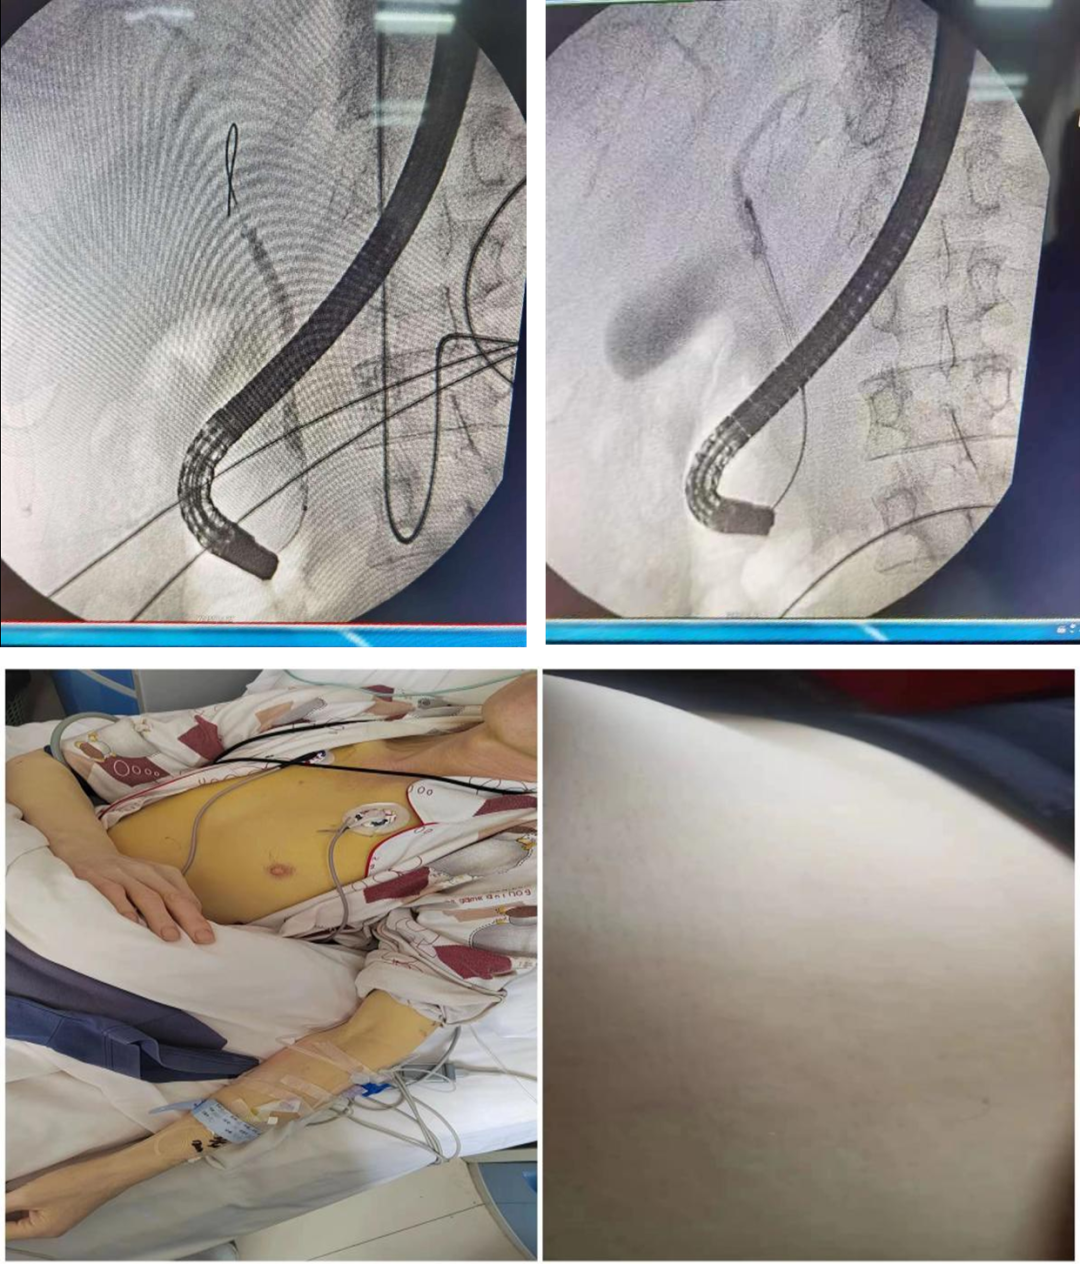

近日,贵医大三附院成功为一名1型糖尿病、化脓性胆管炎胆总管结石患者实施ERCP术(经内镜逆行性胰胆管造影术)+十二指肠乳头切开术+内镜下胆总管网篮取石术+鼻胆引流术。

在全麻后,由路华副主任医师为吴先生实施手术,通过内镜,看到吴先生胆总管下段有一约6mm*6mm的结石嵌顿,切开十二指肠乳头,引流大量脓液,用取石网篮将结石取出,解除了患者胆道梗阻。

术后予以引流及抗感染补液等治疗,休克症状得到纠正,黄疸症状迅速减轻。